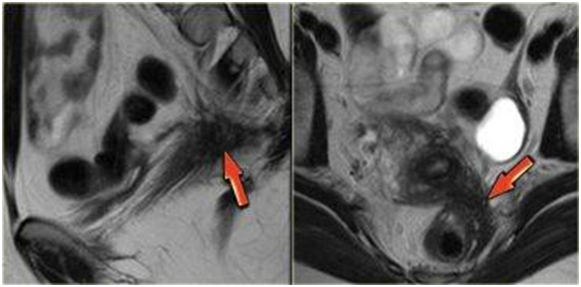

Hình 6. Lạc nội mạc ở sau cổ tử cung

Hình7. Lạc nội mạc quanh cổ tử cung

với hẹp niệu quản trái kèm nang lạc nội mạc buồng trứng trái